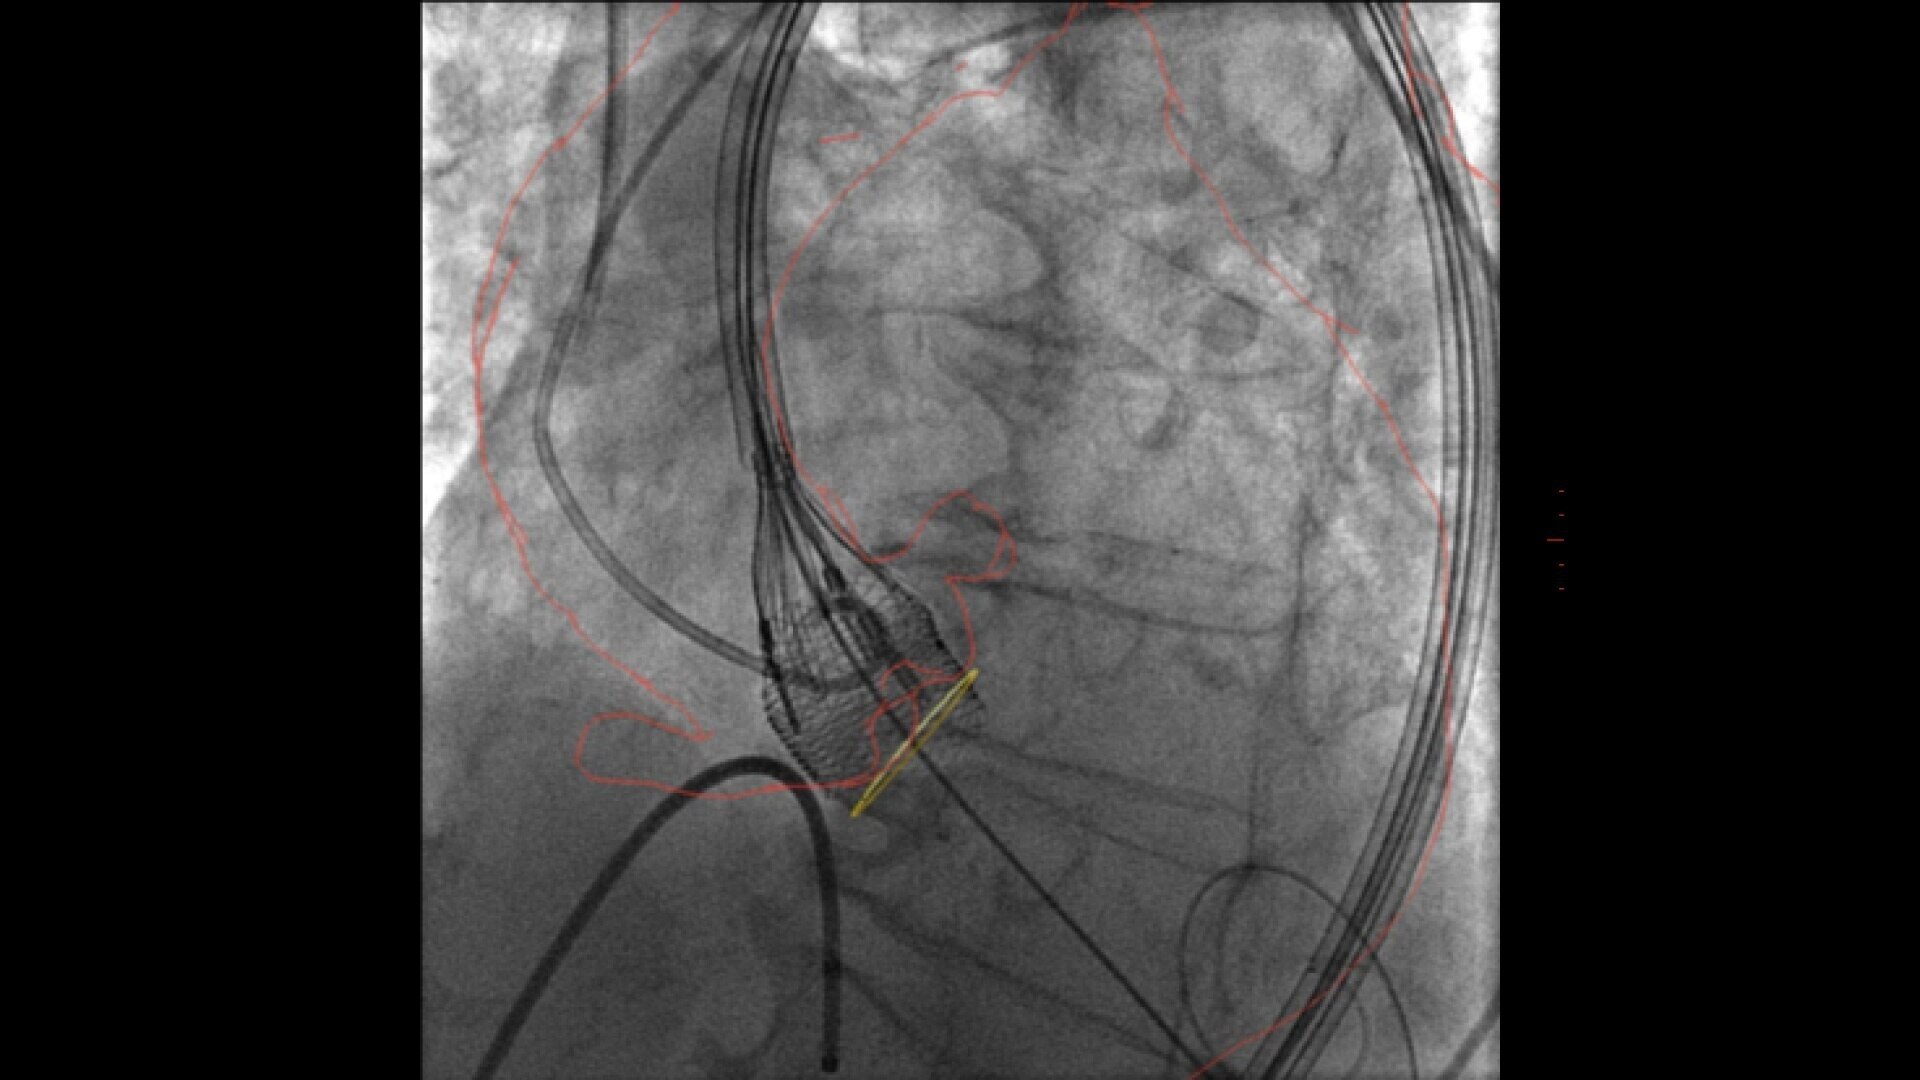

Transcatheter aortic valve implantation

Streamlined workflow for your TAVI procedures

GUIDE

3D fusion guidance enhanced with Calcification Enhancement improves the visualization of moving contrasted structures.